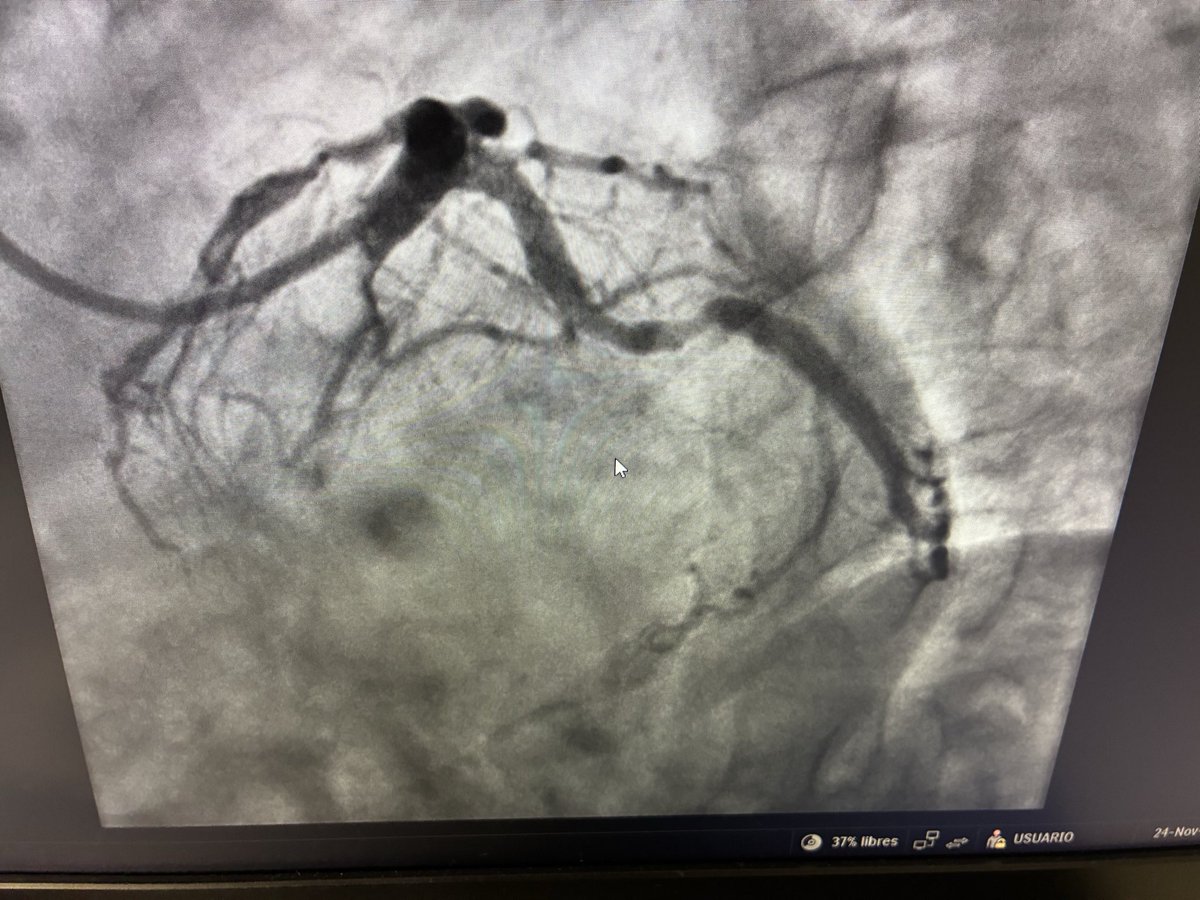

This is the perfect case to randomize in a vulnerable plaque study. Looking forward to the results!

Recta final para la inclusion del @VulnerableTrial con el paciente 500 del RCT aleatorizado. Ya quedan 100 para llegar a los 600 objetivo. Esta vez nos ha tocado en Bellvitge. Caso muy claro de una CF con ALM 2,5 mm2, carga placa 80%, arco lipido >300^ y capa fibrosa de 50 micras